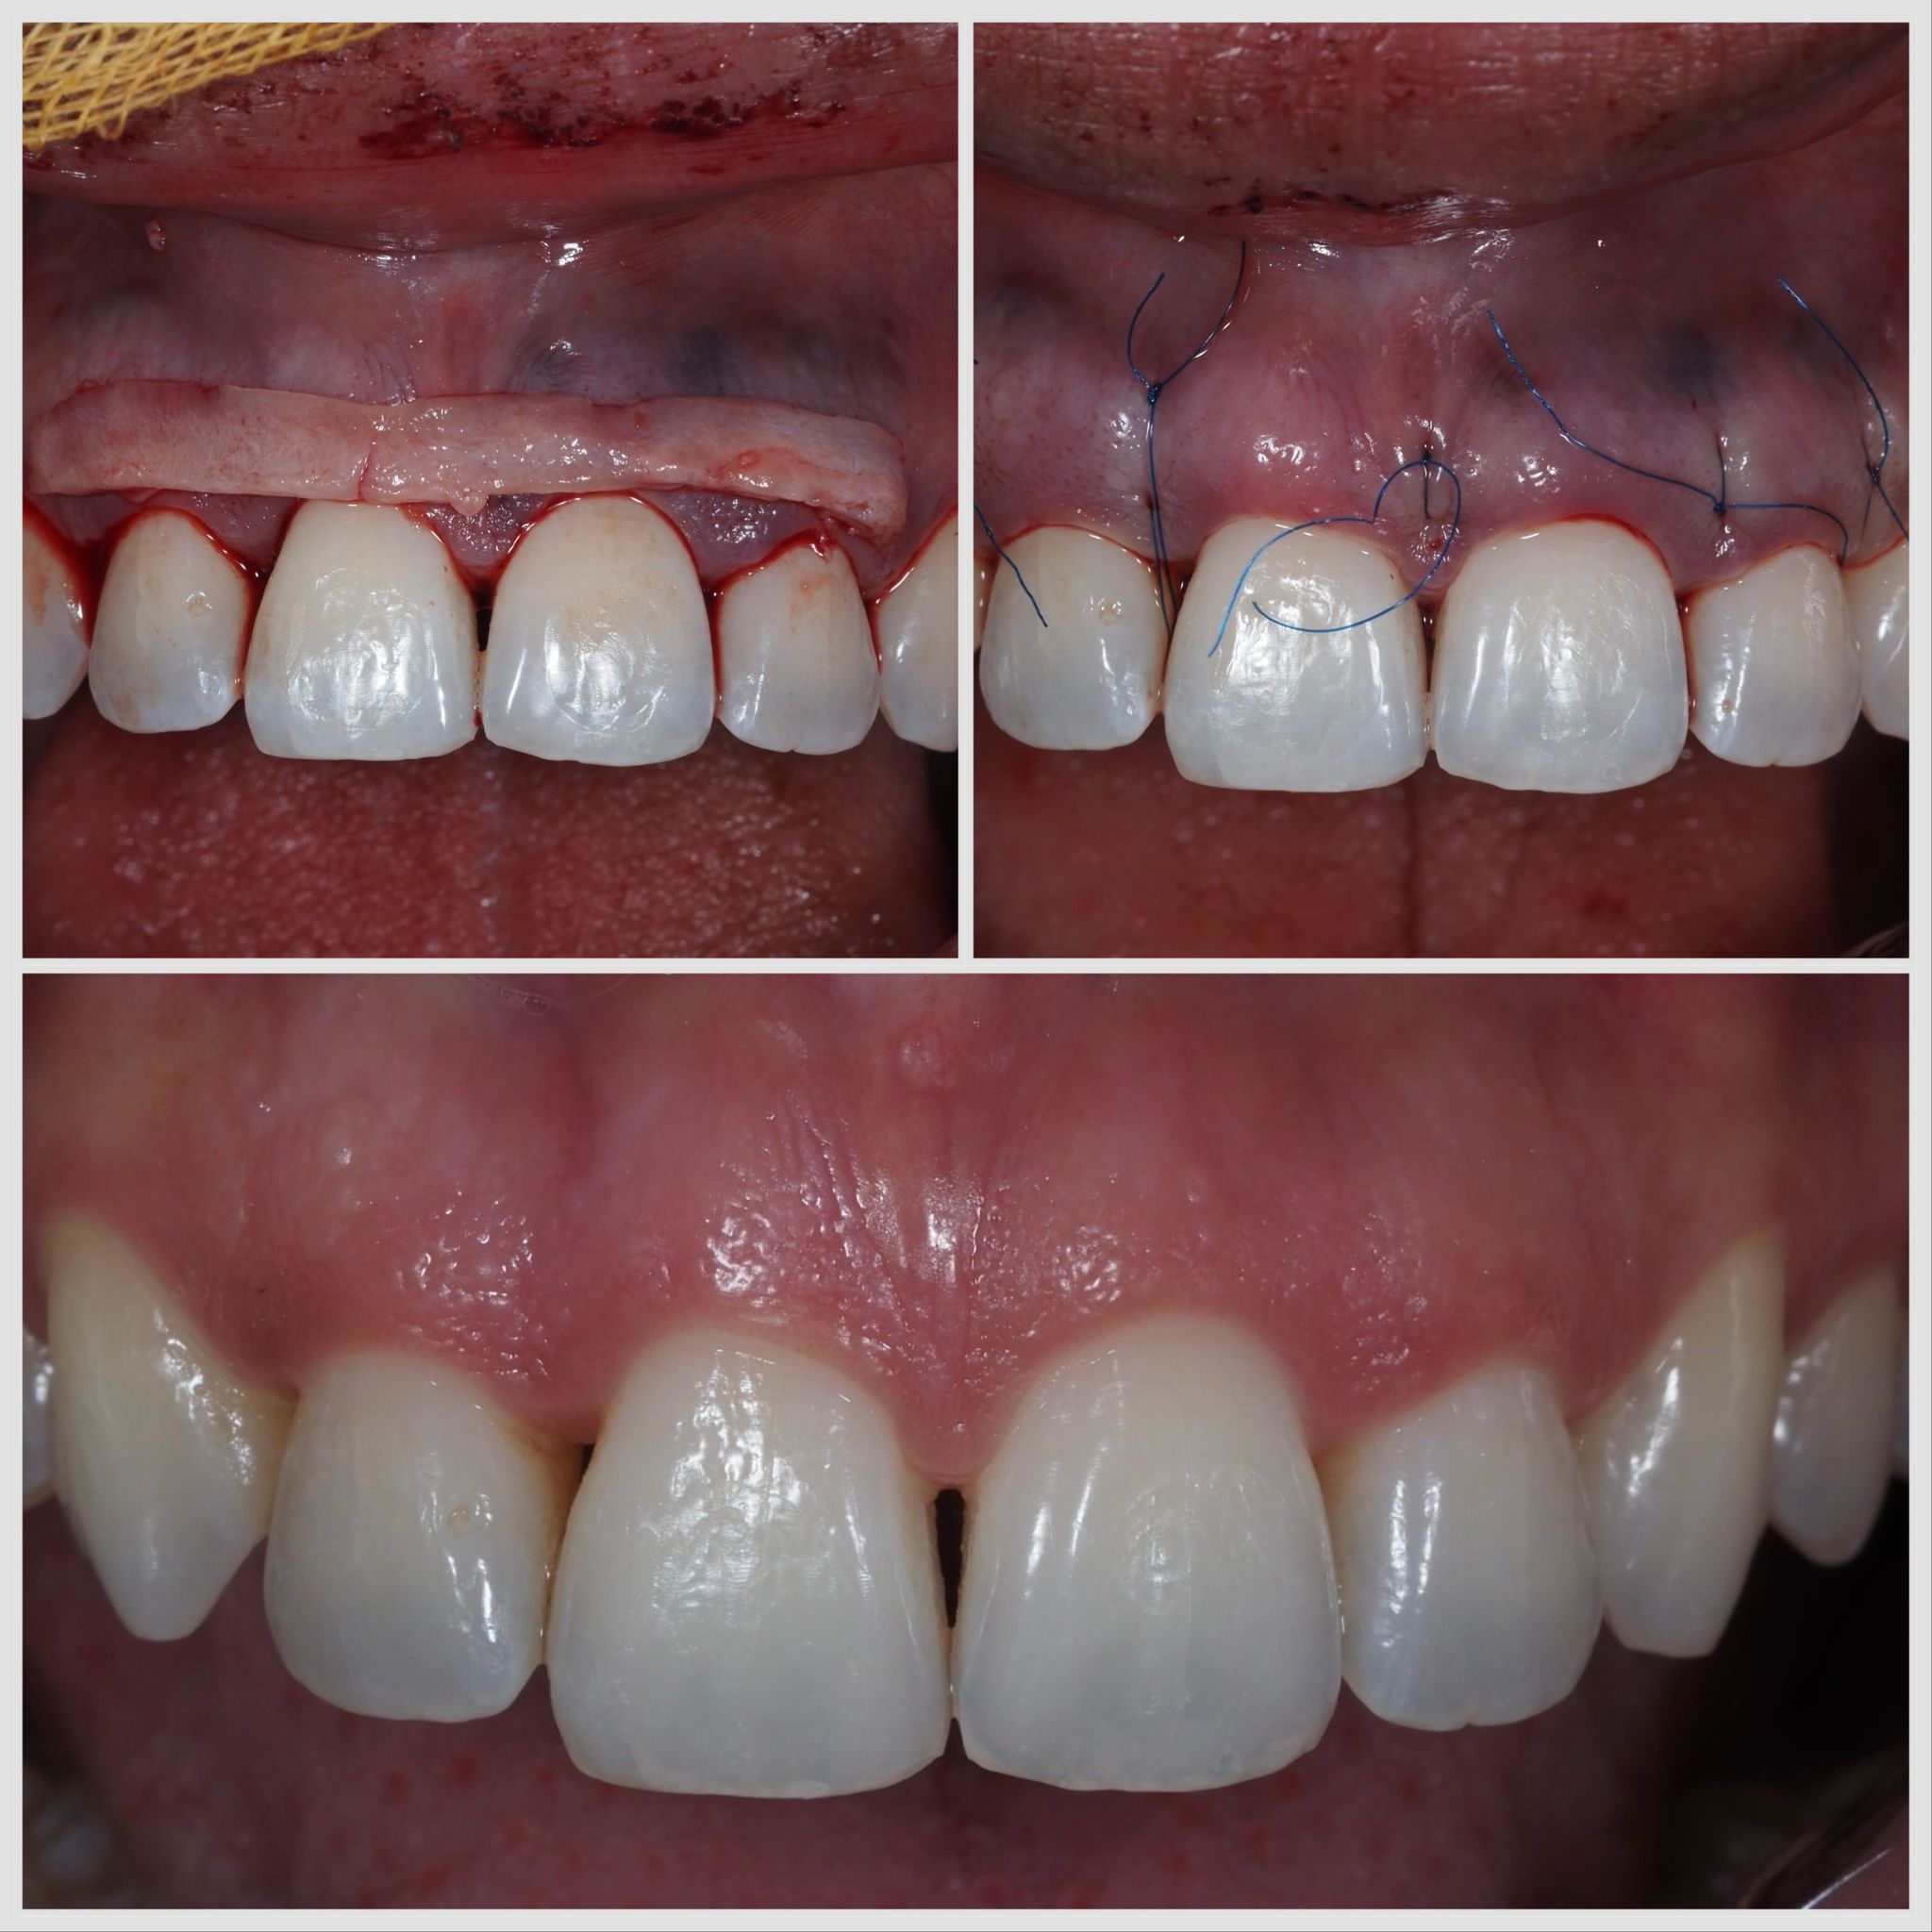

Greffe conjonctive réalisée après traumatisme dentaire avec perte d’incisive en vue d’un bridge cantilever à Apolline Dental Care à Corbeil-Essonnes

Greffe Conjonctif

#parodontologie